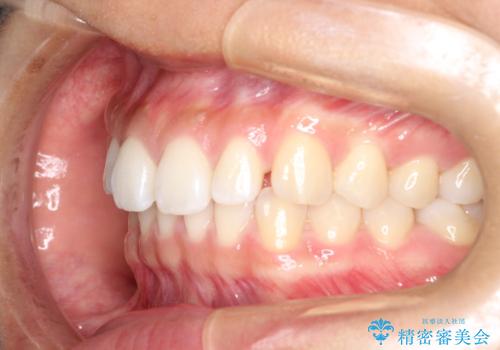

すきっ歯のインビザラインによる目立たない矯正

- すきっ歯を治したいとのことで来院されました。

上下ともに前歯に隙間がありました。

目立たない装置をご希望のためインビザラインで矯正治療を行うこととしました。

使用時間を守っていただけたので、スムーズに治療を終わることができました。